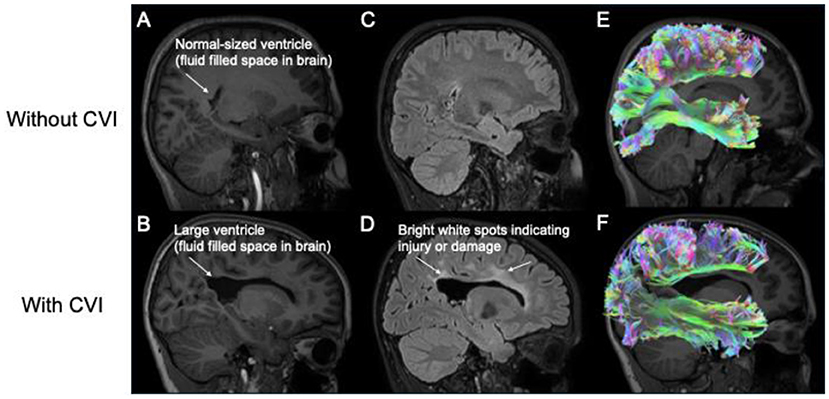

Hjerneafbildning, som involverer brug af teknologi til at generere et billede af hjernen, hjælper forskere med bedre at forstå, hvordan hjernen fungerer hos børn med CVI. Forskere bruger forskellige typer hjerneafbildningsværktøjer, såsom magnetisk resonansafbildning (MRI) eller elektroencefalografi (EEG), for at se strukturen og aktiviteten i forskellige hjerneområder (figur 3).

MR-scanning tager detaljerede billeder af hjernens struktur og producerer et billede af, hvordan hjernen ser ud indvendigt. EEG måler de elektriske signaler, som grupper af celler i hjernen, kaldet neuroner, bruger til at kommunikere med hinanden. Mange dele af hjernen behandler visuel information og er involveret i visuel opmærksomhed. Disse specialiserede hjerneområder ligger langt fra hinanden, men er godt forbundet gennem en række baner, der gør det muligt for dem at kommunikere hurtigt og effektivt (figur 3E, F). Man kan forestille sig forbindelserne mellem hjerneområderne som store byer, der har mange store motorveje, hvor biler kan køre hurtigt over store afstande, og mindre gader, hvor biler kan køre langsommere over kortere afstande. Hos børn bevæger informationen sig typisk hurtigt og effektivt på disse hjerne-motorveje. Men hvis en hjerneskade beskadiger disse baner (som angivet ved de forstørrede ventrikler i figur 3B, de lyse pletter i figur 3D og de reducerede baner i figur 3F), bliver det svært for informationen at komme igennem. Dette er, hvad forskere mener, der kan ske hos børn med CVI: deres hjerner har svært ved at sende og modtage information om den visuelle verden på grund af skader på motorvejene og forbindelserne [3, 4].